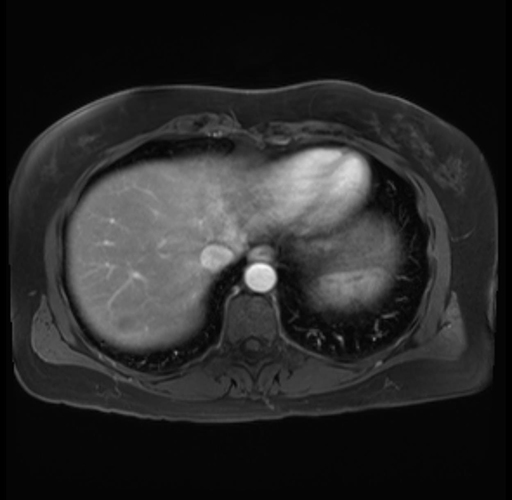

Imaging Analysis

Look through the patient's CT scan to identify any areas of concern for the necessary procedure.

Based on your CT findings, which issue(s) are present and would give reason for "planned slowing down moment(s)" in this case?